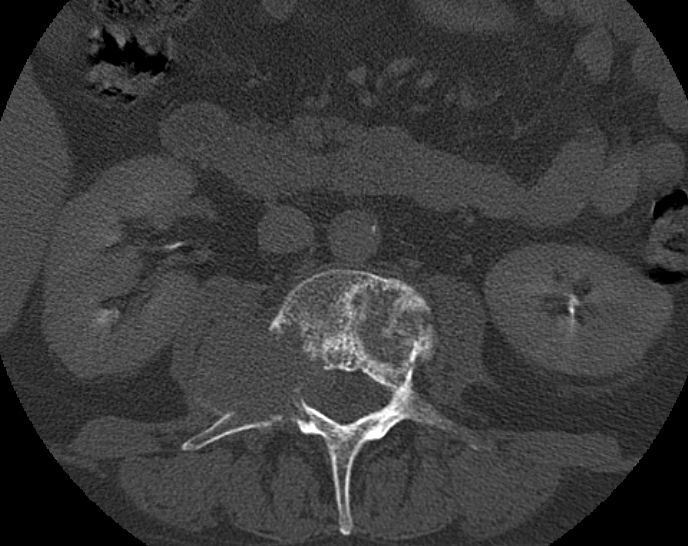

Rückenmarks-Metastasen

48-jährige Patientin mit einem kleinzelligen, neuroendokrinen Bronchialkarzinom. Taubheit der Füße, Kraftminderung und Hypästhesie beider Beine.

Knochenmetastase